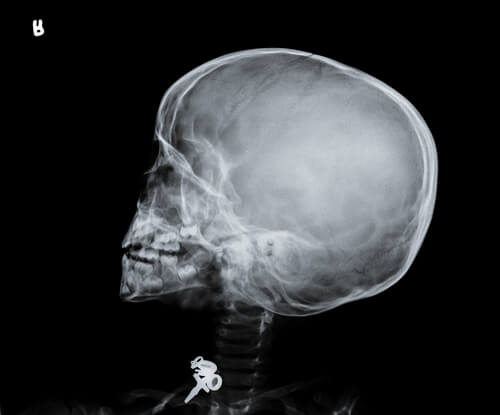

El síndrome del bebé sacudido es conocido como: shaken baby syndrome (SBS) y hace referencia a una forma de abuso físico caracterizada por una serie de signos, dentro de los cuales se incluye la presencia de una lesión cerebral, como puede ser un edema cerebral difuso, y hemorragias retinianas.

En pocas palabras, este síndrome se produce a consecuencia de una sacudida violenta del niño. Aún cuando sea de duración breve, el cerebro del niño puede impactar contra el cráneo y quedar lesionado de forma irreversible.

Hay que tener en cuenta que, durante los primeros meses de vida de un ser humano, el cerebro ocupa la mayor parte de la cabeza, que además es muy pequeña. Por ende, si su cuerpo sufre una sacudida, la masa encefálica choca bruscamente con el cráneo, lo cual puede conllevar a una inflamación y una posible hemorragia interna.